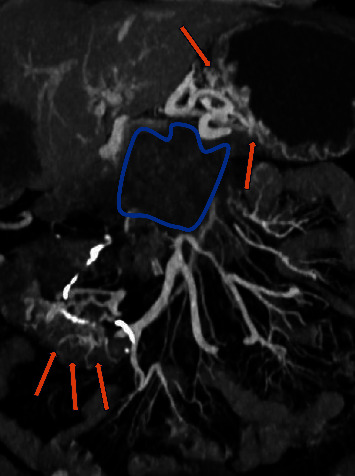

缺血性肠病被认为是厌氧菌感染的高危因素,因为缺血性肠道是厌氧菌生长的理想场所。在此,我们介绍了一例结肠癌晚期患者的病例,该患者罕见地出现了消化道出血和菌血症,病因是一种罕见的厌氧革兰阳性菌--副梭状芽孢杆菌。该患者在慢性肠系膜上静脉-门静脉肿瘤血栓形成和异位静脉曲张破裂的情况下曾多次出现血崩,而菌血症是动脉缺血和静脉充血共同导致的肠道缺血的意外并发症。

Ischemic bowel disease is considered a high-risk factor for infection from anaerobic bacteria, as the ischemic bowel is the perfect ground for their development. Herein, we present the case of an advance stage colon cancer patient with a rare cause of gastrointestinal bleeding and bacteremia due to Clostridium paraputrificum, a rare anaerobic Gram-positive bacterium. The patient had presented with several episodes of hematochezia in the context of chronic superior mesenteric-portal vein tumor thrombosis and rupture of ectopic varices, and the bacteremia was an unexpected complication of the bowel ischemia due to a combination of arterial ischemia and venous congestion.